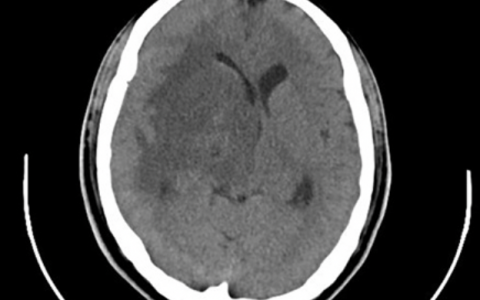

A 67-year-old woman is intubated and mechanically ventilated through a size 6.5 cuffed endotracheal tube after a thoraco-abdominal aneurysm repair(胸腹动脉瘤修复术). During the course of approximately(大约) 20 minutes, her oxygen saturation as measured by pulse oximetry begins to decrease from 97% to 91%, and her endtidal carbon dioxide increases from 36 mm Hg to 52 mm Hg. A flow-volume loop displayed on the ventilator is shown below.

流量回路显示呼吸机回路泄漏。吸气量大于呼出量。这可能位于回路的任何水平,但破裂的球囊通常会导致泄漏。在回路泄漏的情况下,减少潮气量将减少分钟通气量并增加呼气末二氧化碳,并可能通过允许肺泡萎陷而恶化氧合。不适合使用吸入性支气管扩张剂,因为没有急性阻塞性肺病的证据。由于没有胸内阻塞的证据,因此气管插管吸引不太可能有效。可能需要对患者重新插管,但这不是下一步,因为套囊可能需要简单的空气再注入。